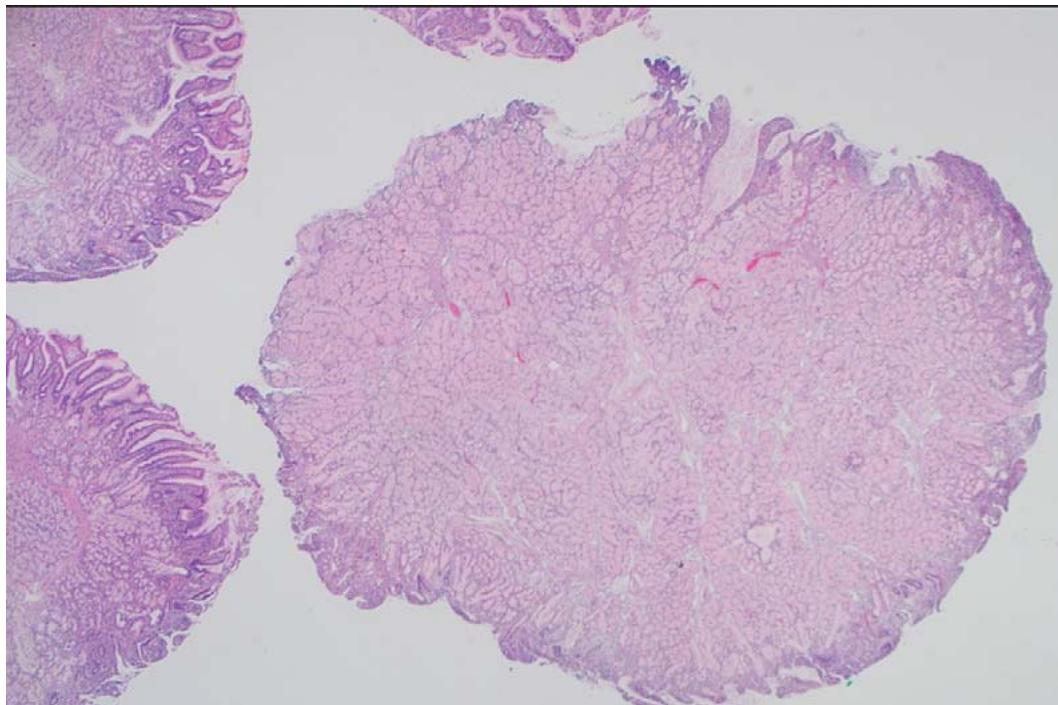

A 64-year-old male with history of heart failure with reduced ejection fraction, chronic renal failure stage 5, coronary artery disease, diabetes mellitus, hypertension, stroke, benign prostatic hyperplasia and tobacco use disorder, presented to the hospital for a nephrology follow up visit. Detection of combined iron deficiency and chronic disease anemia (decreased hemoglobin $6.6\mathrm{g / dl}$, hematocrit $20.6\%$ and iron 34 ug/dL; with normal MCV 91.7 fL, and ferritin 69 ng/ml) prompted upper endoscopy and colonoscopy. The upper endoscopy showed a $1.5\mathrm{cm}$, pink-tan polyp in the duodenum, which was resected. The histopathological examination revealed BGA/BGH type 3 without dysplasia or malignancy (Figure 1 & 2). Immunohistochemistry revealed intact expression of DNA mismatch repair proteins (MLH1, MSH2, MSH6 and PMS2) supporting lack of microsatellite instability. Due to the rarity of the lesion next generation sequencing (Oncomine Focus, ThermoFisher) was performed on extracted DNA revealing a KRAS G12D genetic alteration. In addition, the colonoscopy revealed three tubular adenomas (one $0.4\mathrm{cm}$ pedunculated polyp in the ascending colon and two sessile polyps ranging from 0.3 to $0.5\mathrm{cm}$ in the transverse colon). Of note, the patient died three months later due to respiratory failure from SARS-CoV-2 infection.

Figure 1: Photomicrograph of Brunner gland nodule (H & E x20)